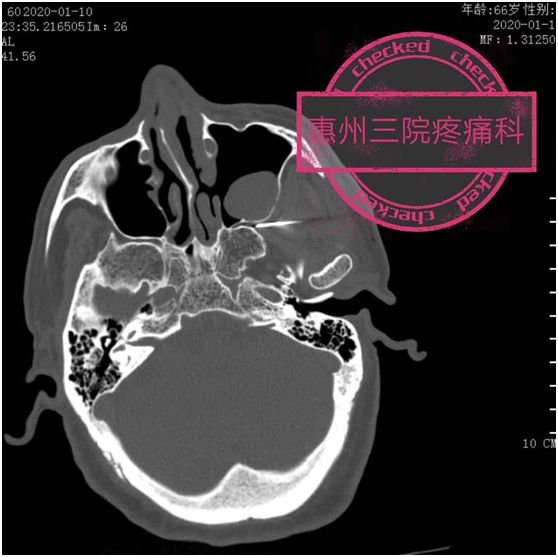

在CT引導(dǎo)下,經(jīng)顳側(cè)顴弓下穿刺進(jìn)入翼腭窩(即蝶腭神經(jīng)節(jié)的“家”),將射頻電極送至蝶腭神經(jīng)節(jié),開(kāi)啟脈沖射頻模式,調(diào)整合適參數(shù),對(duì)蝶腭神經(jīng)節(jié)調(diào)整,達(dá)到治療目的。

知道開(kāi)關(guān)在哪,可要找到它可沒(méi)那么容易。值得欣喜的是,惠州三院疼痛科醫(yī)生根據(jù)豐富的介入治療經(jīng)驗(yàn),借助CT輕松找到了它,并通過(guò)微創(chuàng)精準(zhǔn)蝶腭神經(jīng)節(jié)脈沖射頻術(shù),為眾多鼻炎患者解除了頑疾!